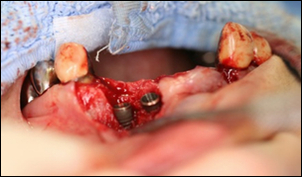

短い期間で治療を終わらせる為に、出来るだけ組織へのダメージを小さくするために最低限の傷口でインプラントの埋入を行いました。

歯を抜いた写真です。

インプラントを入れる穴を開けた写真です。

インプラントを埋入した写真です。

写真から見てわかるように、出来るだけ歯ぐきを切らずにインプラントを入れています。

通常インプラント手術では、骨が直視できる状態の方が埋入を簡単に行えるため骨が露出するまで歯ぐきを切開します。ですが歯ぐきを一度はぐと血流が途絶え、傷の回復に時間がかかります。

上の写真のように歯ぐきをはがずにインプラントを埋入することをフラップレスといいます。

当院ではできるだけフラップレスを行っています。